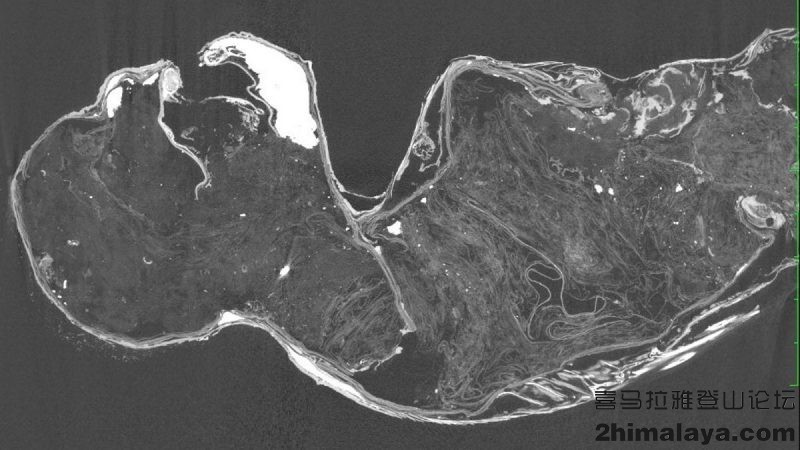

仓敷大学的研究人员用X射线,CT扫描,放射性碳测年方法和DNA分析了动物。他们希望在不对其造成破坏的情况下了解动物的物种。并非是猴子-鱼类创造出的动物,他们发现这种美人鱼根本没有估价。仅有一块颌骨。

这种神秘动物的身体使用布,纸,棉花和针制作,用沙子和木炭膏粘合,上面附上一层河豚鳞片。头部的毛发源自无法判断的哺乳动物,指甲则是角蛋白。此外还有鱼皮,牙齿源自一种食人鱼,作为这种创造出来动物的嘴部。美人鱼的胃部则来源于一种鱼类,可能是黄花鱼。

扫描显示其颌骨